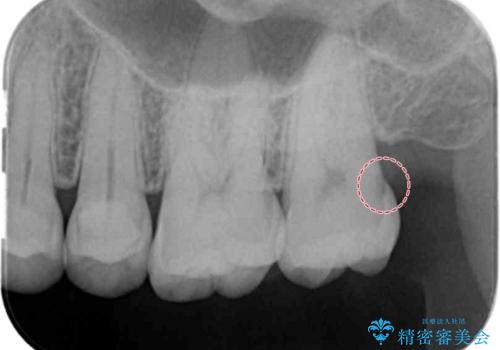

- 検査の結果、レントゲン画像上で虫歯が確認されたため治療をしていくこととなりました。

白くて精度の高いものをご希望されたためセラミックインレーでの治療を行いました。

- 右上6 セラミックインレー 77,000円費用は治療当時の料金となります